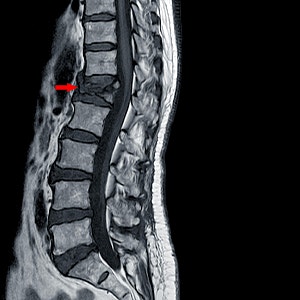

흉추 12번(T12) 압박골절 확인됨

척추체 전방의 함몰, 쐐기형 변형(wedge deformity) 관찰해당 부위 국소 후만 변형 유발

2. Cobb Angle (후만각) 측정 결과

T11–L1 기준 Cobb angle: 약 28도 ±2도

이는 정상 상한선을 초과함

T11–L1 정상 후만각은 0도에서 10도 사이로 알려져 있음

(정상 범위 최대 15도, 평균은 약 5도 전후)

해당 환자의 연령대(56세 여성)를 고려해도 이 구간에서 자연 후만 20도 이상은 드물며, 사고 전에는 비교적 정렬이 유지되었을 가능성이 높음

사고 이후 영상상 Cobb angle 약 28도로 측정되며, 사고 전 비교적 정상 정렬(10도 이내)로 가정하면 15도 이상의 각 증가로 해석 가능

영상 소견상 압박골절 및 쐐기형 변형은 단순 퇴행성 변화보다 외상성 기전이 타당

56세 여성 환자의 흉추 12번 부위 압박골절에 따른 구조적 변형이 영상에서 확인됩니다. Cobb angle(T11–L1)은 약 28도이며, 이는 정상 상한선(15도)을 초과하고, 사고 전 정렬이 정상(0~10도)이었다면 최소 15도 이상의 후만각 증가로 판단됩니다.